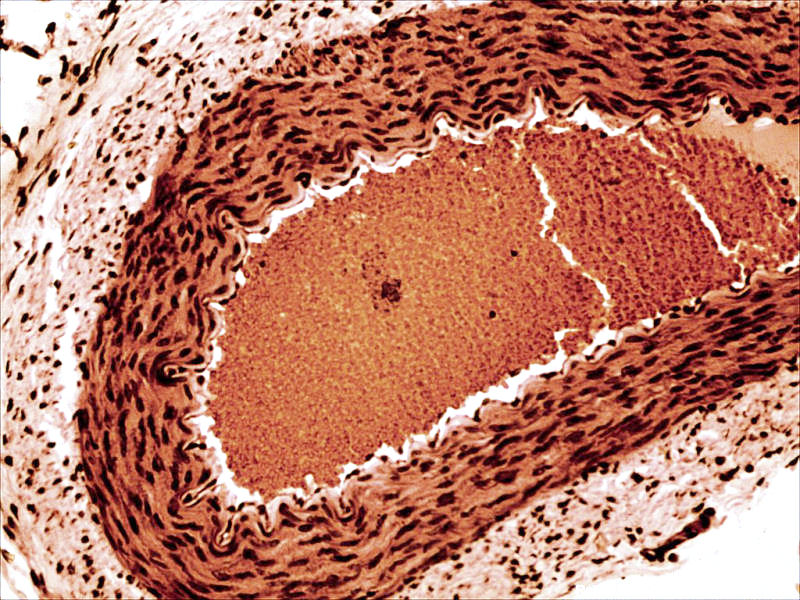

back Rabbit arteriole

Source: http://www.3dham.com/microgallery/

Author: John Alan Elson